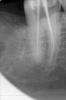

Снежана Опубликовано 25 апреля, 2013 Поделиться Опубликовано 25 апреля, 2013 попались почти подряд 2 шестерки с 5-тью каналами обнаружены без всякого микроскопа. http://img-fotki.yandex.ru/get/6435/32678997.1/0_9f73d_14fafb97_L.jpghttp://img-fotki.yandex.ru/get/5637/32678997.1/0_9f73e_40b93823_L.jpg http://img-fotki.yandex.ru/get/6431/32678997.1/0_9f73c_50036240_L.jpg 9 Ссылка на комментарий

Снежана Опубликовано 26 апреля, 2013 Автор Поделиться Опубликовано 26 апреля, 2013 Снежана, круто Спасибо до этого была еще парочка зубов с такой анатомией, чтобы прямо отдельный ММ канал до апекса или сходился к апикальной трети. но к сожалению до обтурации они не добрались. видимо сбежали туда, где подешевле.и фсё... за последние пару лет. Ссылка на комментарий

Снежана Опубликовано 29 апреля, 2013 Автор Поделиться Опубликовано 29 апреля, 2013 посмотрите каналы опять 3 или я пропустил,дистальный белым сразу прошел 0,6 протейпером,он особо и не цеплял,широкийДенис, на втором снимке выглядит как будто дистальных каналов 2, но может он и 1, просто очень широкий и штифт там болтается.про медиальные по снимкам ничего не могу сказать, нужно смотреть сам зубик. из того, что попадалось мне - если в мезиальной системе обнаруживалось 3 канала, то устья щечного и язычного находились друг от друга достаточно далеко.вы попробуйте заполнить каналы рентгенконтрастом, что-нить вроде метапасты и сделать повторно снимки, лучше повторить проекцию вашего второго снимка, тогда будет яснее в дистальном корне один канал или 2. Ссылка на комментарий